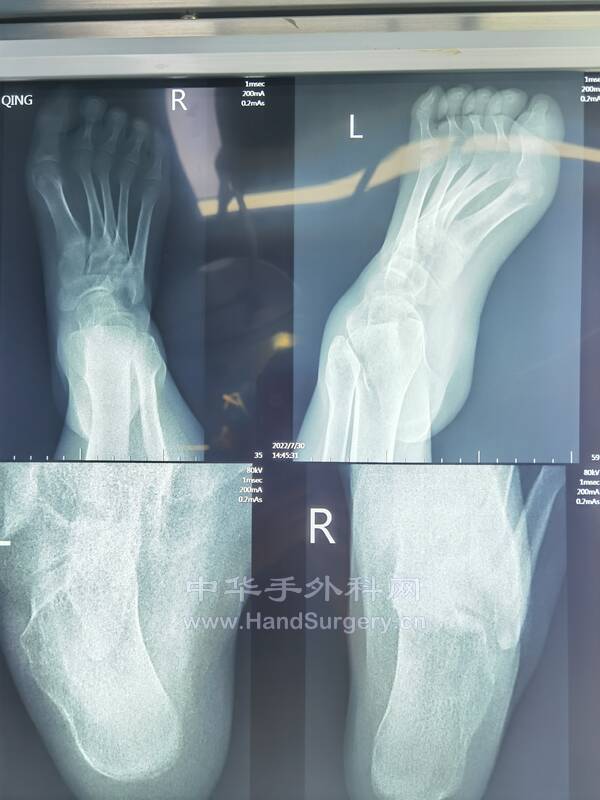

明日需要手术的右足马蹄外翻足,扁平足小患者资料(图18--41)

明日需要手术的右足马蹄外翻足,扁平足小患者资料(图1-24)